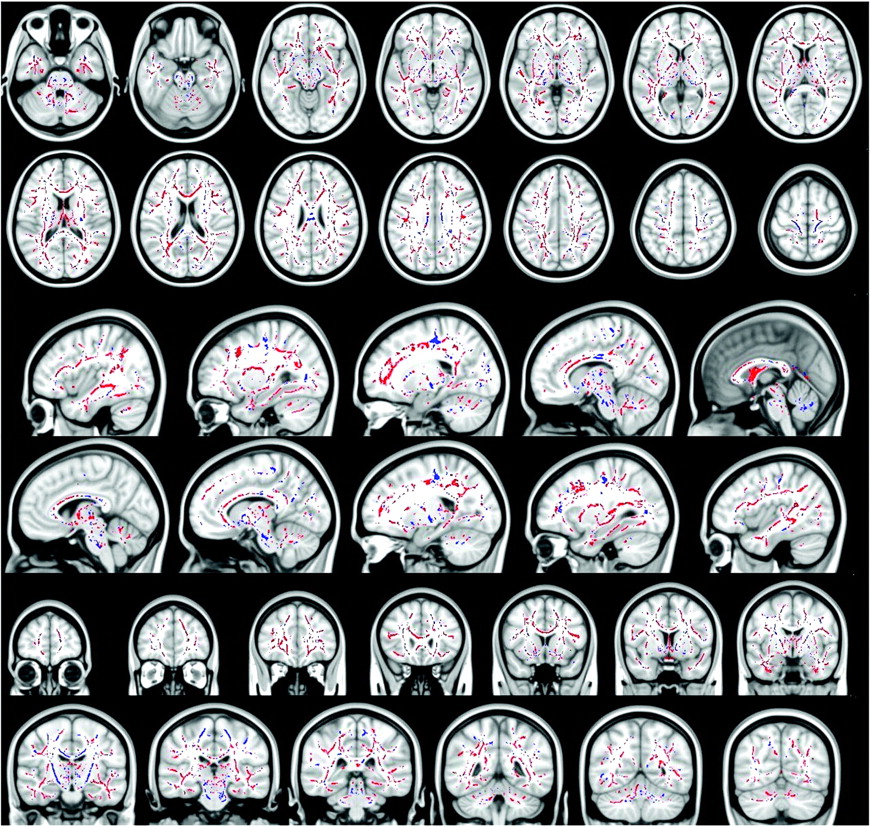

Blue voxels show the regions within and outside the CST, where the FA is significantly reduced in patients with ALS with T1 MTC hyperintense signal intensity compared with patients with ALS without T1 MTC hyperintense signal intensity (all P values < .05, corrected at the cluster level). Red voxels show the regions where the FA is significantly increased in patients with ALS with T1 MTC hyperintense signal intensity compared with patients with ALS without T1 MTC hyperintense signal intensity (all P values < .05, corrected at cluster level). In the CC, patients with T1 MTC hyperintense signal intensity compared with patients without T1 MTC hyperintensity show a significantly lower FA only in the posterior aspect of the body of the CC, whereas they show higher FA in the entire CC, in the splenium, in the genu, and in the anterior body.

Patients with T1 MTC hyperintense signal intensity along the CST had significantly lower FA (all P values <.01) compared with patients without T1 MTC hyperintensity (Table 2 and Fig 2). In particular, lower FA was found bilaterally from the subcortical precentral gyrus passing through the centrum semiovale, the posterior limb of the internal capsule, the pons, and middle cerebellar peduncle. Regarding the CC, patients with T1 MTC hyperintense signal intensity along the CST compared with patients without it showed a significantly lower FA only in the posterior aspect of the body of the CC (T1 MTC hyperintense mean FA 0.528 ± 0.015 versus T1 MTC absent mean FA 0.536 ± 0.015), whereas they showed higher FA in the entire CC, in the splenium, in the genu, and in the anterior body (mean FA in the entire CC T1 MTC hyperintense, 0.580 ± 0.018, versus T1 MTC absent mean FA, 0.569 ± 0.018). Most interesting, in the regions outside the CST (the white matter adjacent to the superior and middle frontal gyrus, the parietal and temporal white matter, the anterior limbs of internal capsule, and the external capsule), the patients with T1 MTC high signal intensity showed increased FA (mean FA in the frontal white matter, 0.243 ±0.014; mean FA in the temporal white matter, 0.268 ± 0.013; mean FA in the parietal white matter, 0.236 ± 0.016) compared with the group of patients without T1 MTC hyperintense signal intensity (mean FA frontal white matter, 0.234 ± 0.013; mean FA in the temporal white matter, 0.245 ± 0.012; mean FA in the parietal white matter, 0.212 ±0.015).

Difference in FA between Patients with ALS with T1 MTC Hyperintense Signal Intensity and Controls

Patients with ALS with and without T1 MTC hyperintense signal intensity along the CST had significantly lower FA (all P values <.05) in several confluent regions within and outside the CST compared with healthy controls. These results are consistent with previous DTI studies.28,35 In particular, lower FA was found bilaterally in the pons, middle cerebellar peduncle, posterior limb of the internal capsule, the centrum semiovale, and subcortical precentral gyrus. Patients also showed a significantly lower FA throughout the white matter of both hemispheres, in particular underneath the premotor, primary sensory, frontal, and prefrontal cortices, adjacent to the superior and middle frontal gyri, in the parietal and temporal white matter, and in the anterior limbs of the internal and the external capsules. A marked reduction of FA was found throughout the entire CC.

Regarding DTI, the most interesting result of this study is that there were regional differences in white matter FA between patients with T1 MTC hyperintense signal intensity and patients without it. Patients with T1 MTC abnormal signal intensity showed lower FA strictly limited to the motor network and the posterior aspect of the body of the CC without extramotor FA reductions, whereas patients without this sign showed FA reductions in several confluent regions within and outside the CST (frontal, temporal, parietal lobes) and in the whole CC.